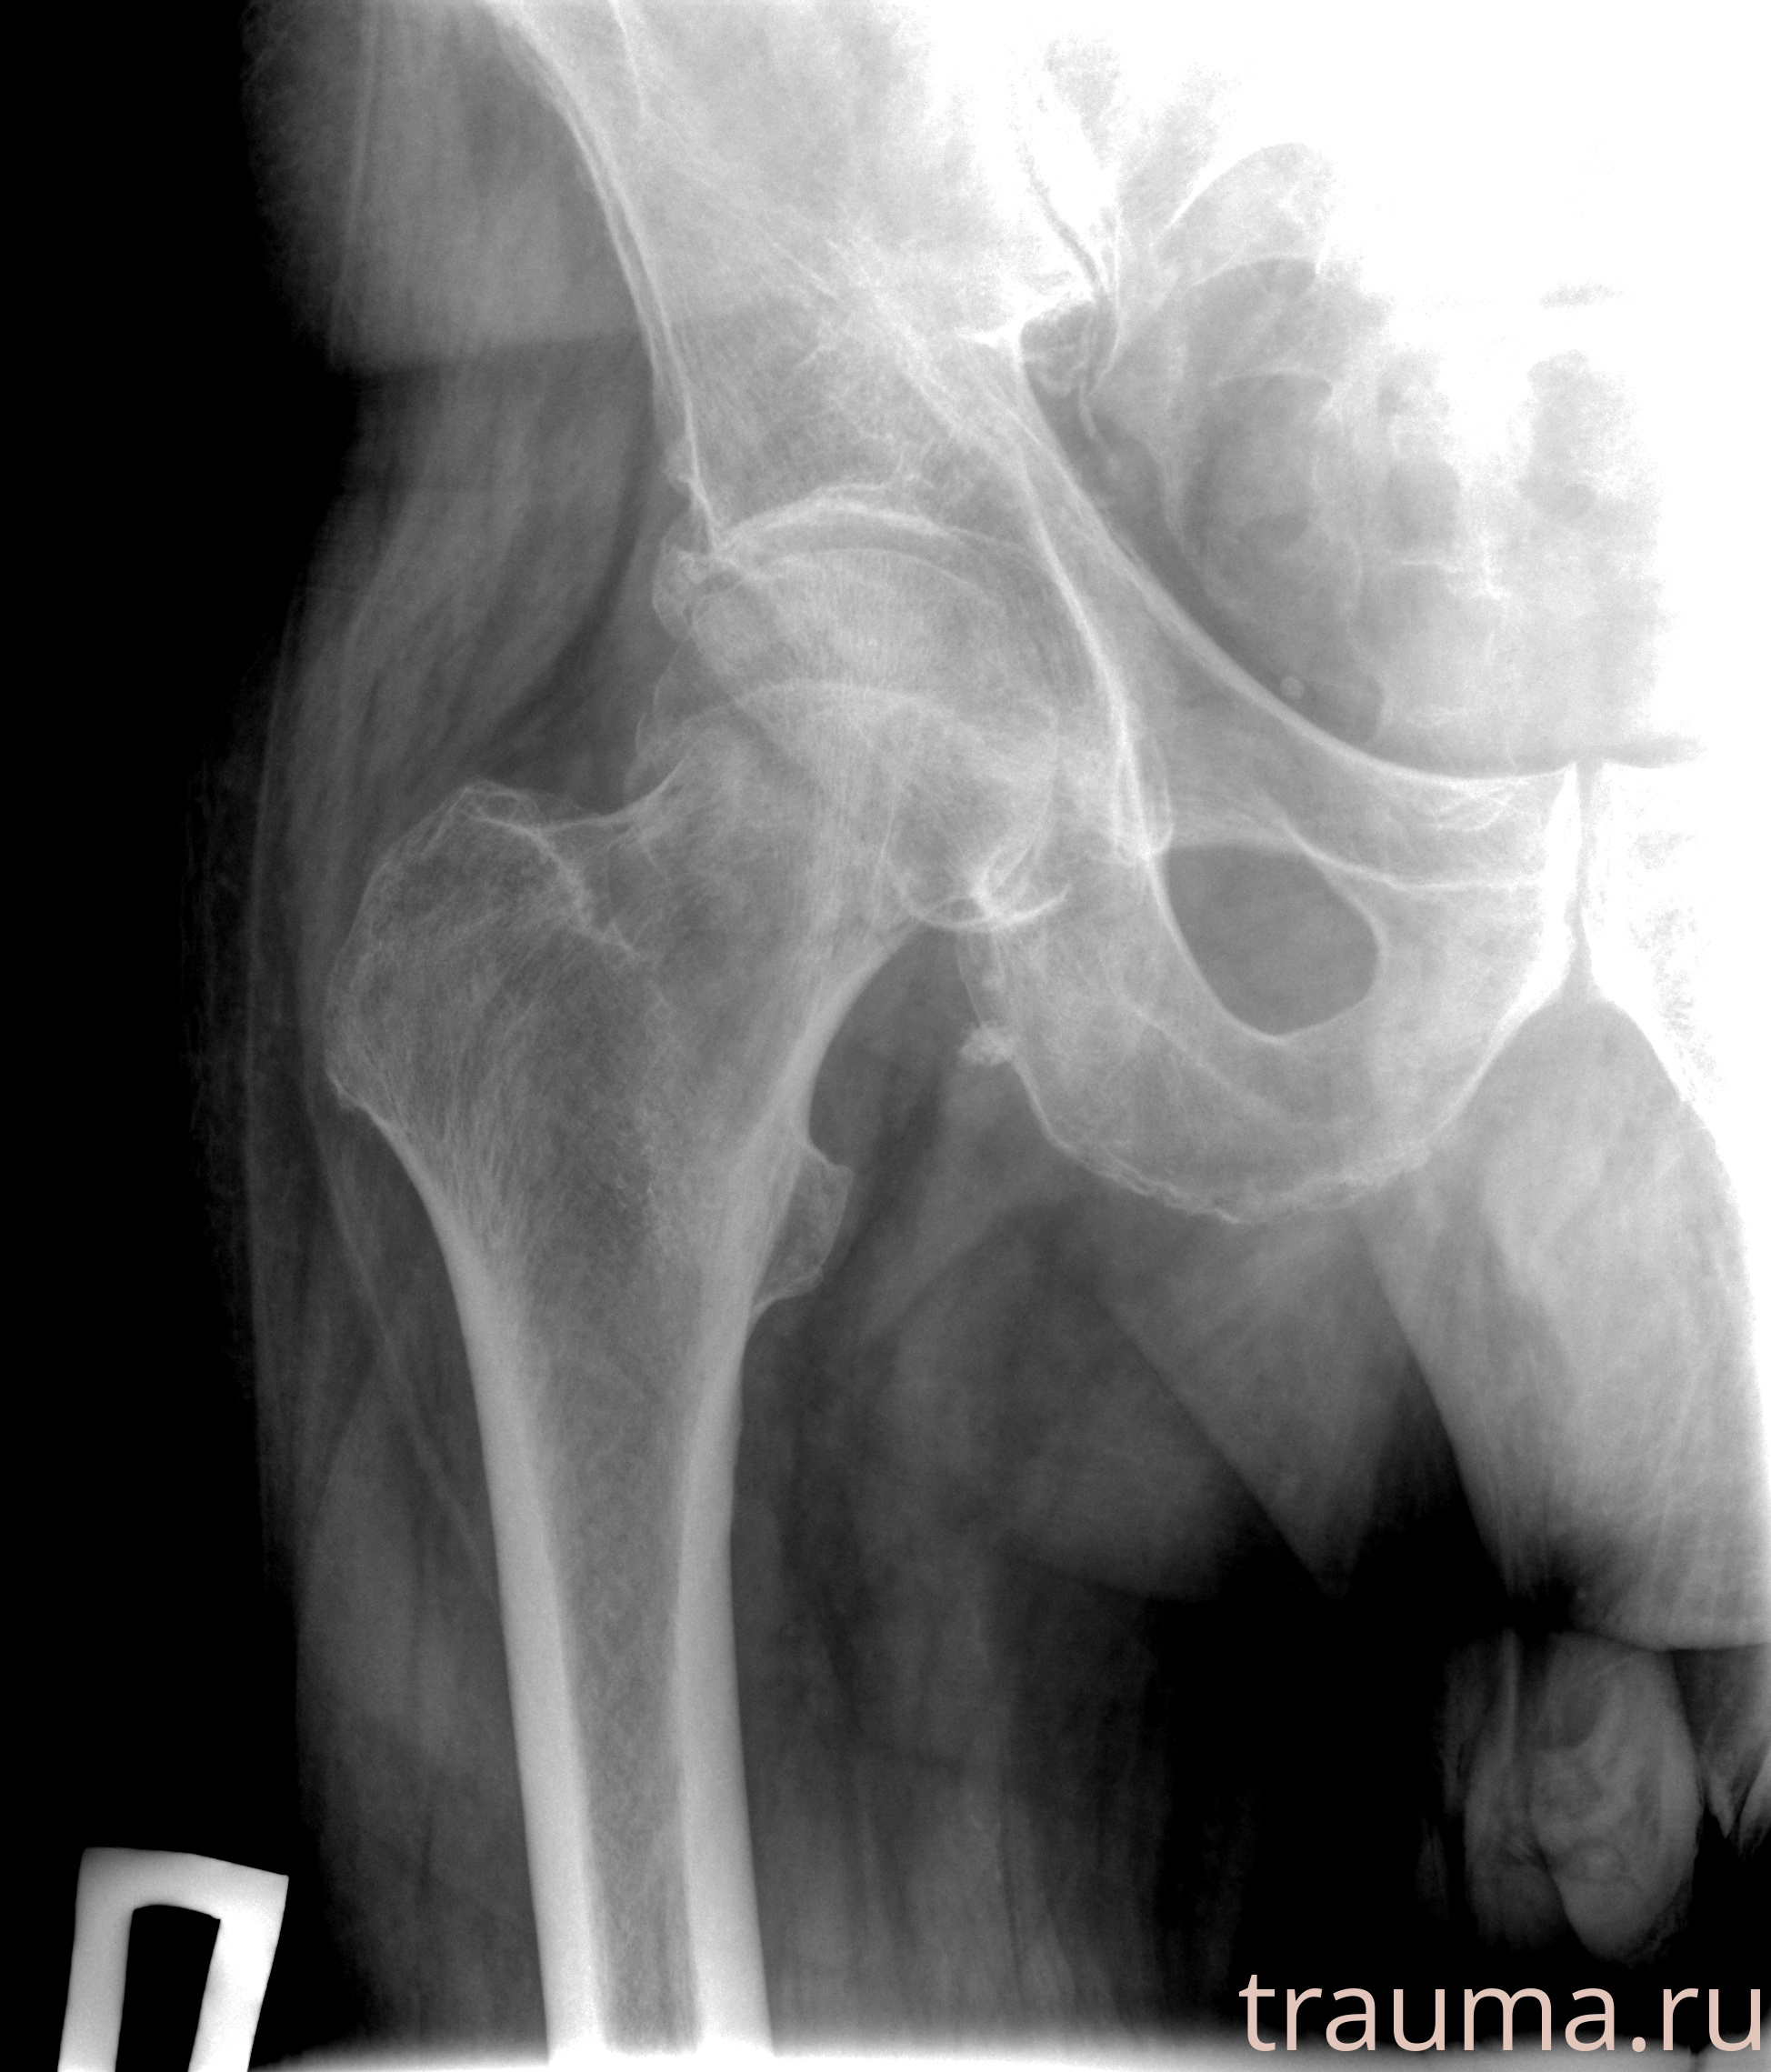

Рентгенограммы

Рентген на дому: по вашему адресу приезжает врач-рентгенолог, травматолог-ортопед с мобильным рентгеновским аппаратом, проводит диагностику травмы или заболевания, делает необходимые рентгенограммы, дает рекомендации по дальнейшему лечению. Получить качественные снимки в домашних условиях возможно благодаря уникальной методике, разработанной МосРентген Центром для института  Склифосовского